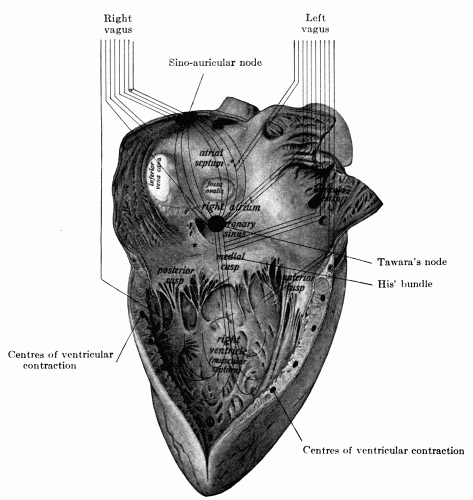

38. Right side of the heart showing distribution of the two vagus nerves127

39. Normal electrocardiogram128

53. Schematic distribution of right and left vagus145

54. Blood pressure record from a normal reaction to ether149